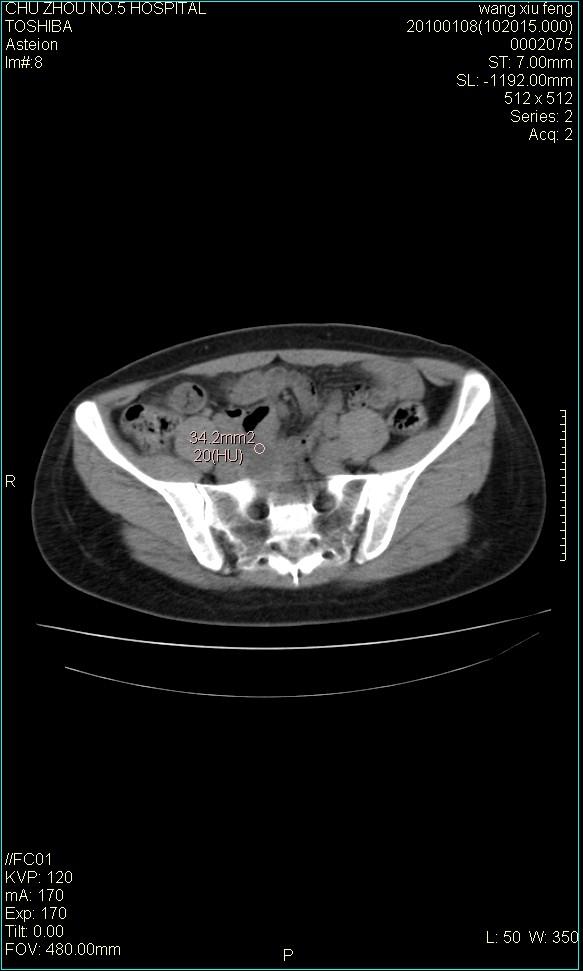

f-41,左乳腺ca术后4年,b超示:子宫右上方囊性包块约5.5*3.4cm,前日行胸部ct平扫未见明显异常。

囊腺瘤,转移瘤不排除。

考虑右侧卵巢囊腺瘤?

右侧卵巢囊肿或小囊腺瘤。

考虑肠系膜囊肿可能性大

考虑右侧卵巢囊腺瘤?建议增强!

考虑右侧卵巢囊腺瘤。

考虑右侧卵巢囊性占位性病变(囊肿?囊腺瘤?)。